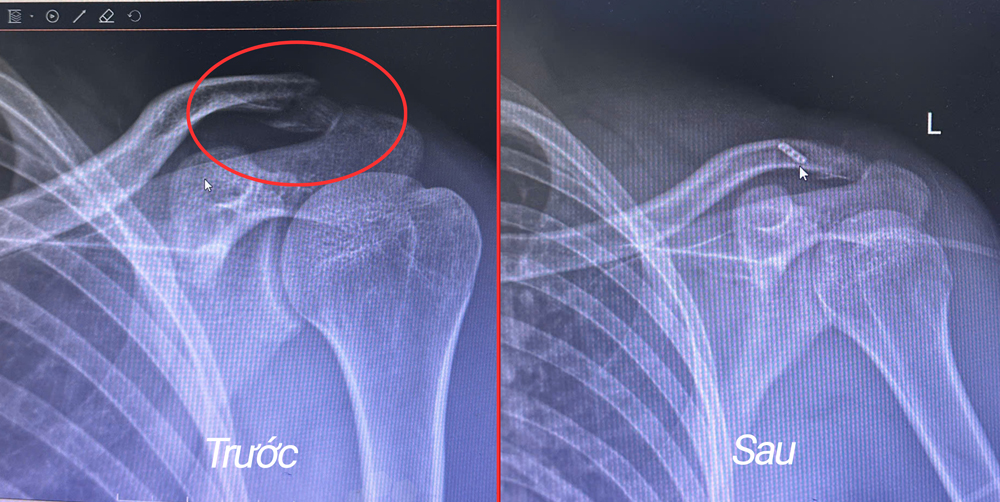

Kết quả chụp X-quang cho thấy: bệnh nhân bị gãy đầu ngoài xương đòn trái. Tiến hành hội chẩn, tư vấn cho bệnh nhân và người nhà bệnh nhân, các bác sĩ đã chỉ định phẫu thuật nội soi kết hợp xương đòn trái – kỹ thuật tiên tiến với đường mổ nhỏ (chỉ 1–2cm), giúp bệnh nhân hồi phục nhanh, giảm đau tốt và không để lại vết sẹo dài.

Hình ảnh X-quang trước và sau phẫu thuật nội soi kết hợp xương đòn của bệnh nhân V.

Ca mổ do BSCKII. Vũ Minh Hải – Trưởng khoa Ngoại 2, Bệnh viện Hữu nghị Lạc Việt cùng ekip trực tiếp thực hiện. Trong quá trình phẫu thuật, các bác sĩ đã sử dụng loại chỉ “siêu bền” để kéo phần xương đòn gãy bị bật lên về đúng vị trí giải phẫu và cố định chắc chắn. Phương pháp này còn giúp người bệnh không cần phải trải qua cuộc mổ lần hai để lấy dụng cụ như khi đặt nẹp hoặc một số kỹ thuật cố định khớp cùng đòn khác.